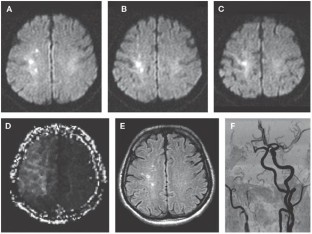

Hendrikse J et al. (2002) Magnetic resonance angiography of collateral compensation in asymptomatic and symptomatic internal carotid artery stenosis. J Vasc Surg 36: 799–805

Hendrikse J (2001) Collateral ability of the circle of Willis in patients with unilateral internal carotid artery occlusion: border zone infarcts and clinical symptoms. Stroke 32: 2768–2773

Hartkamp MJ et al. (1999) Circle of Willis collateral flow investigated by magnetic resonance angiography. Stroke 30: 2671–2678

Patel MR et al. (1995) Preoperative assessment of the carotid bifurcation: can magnetic resonance angiography and duplex ultrasonography replace contrast arteriography? Stroke 26: 1753–1758